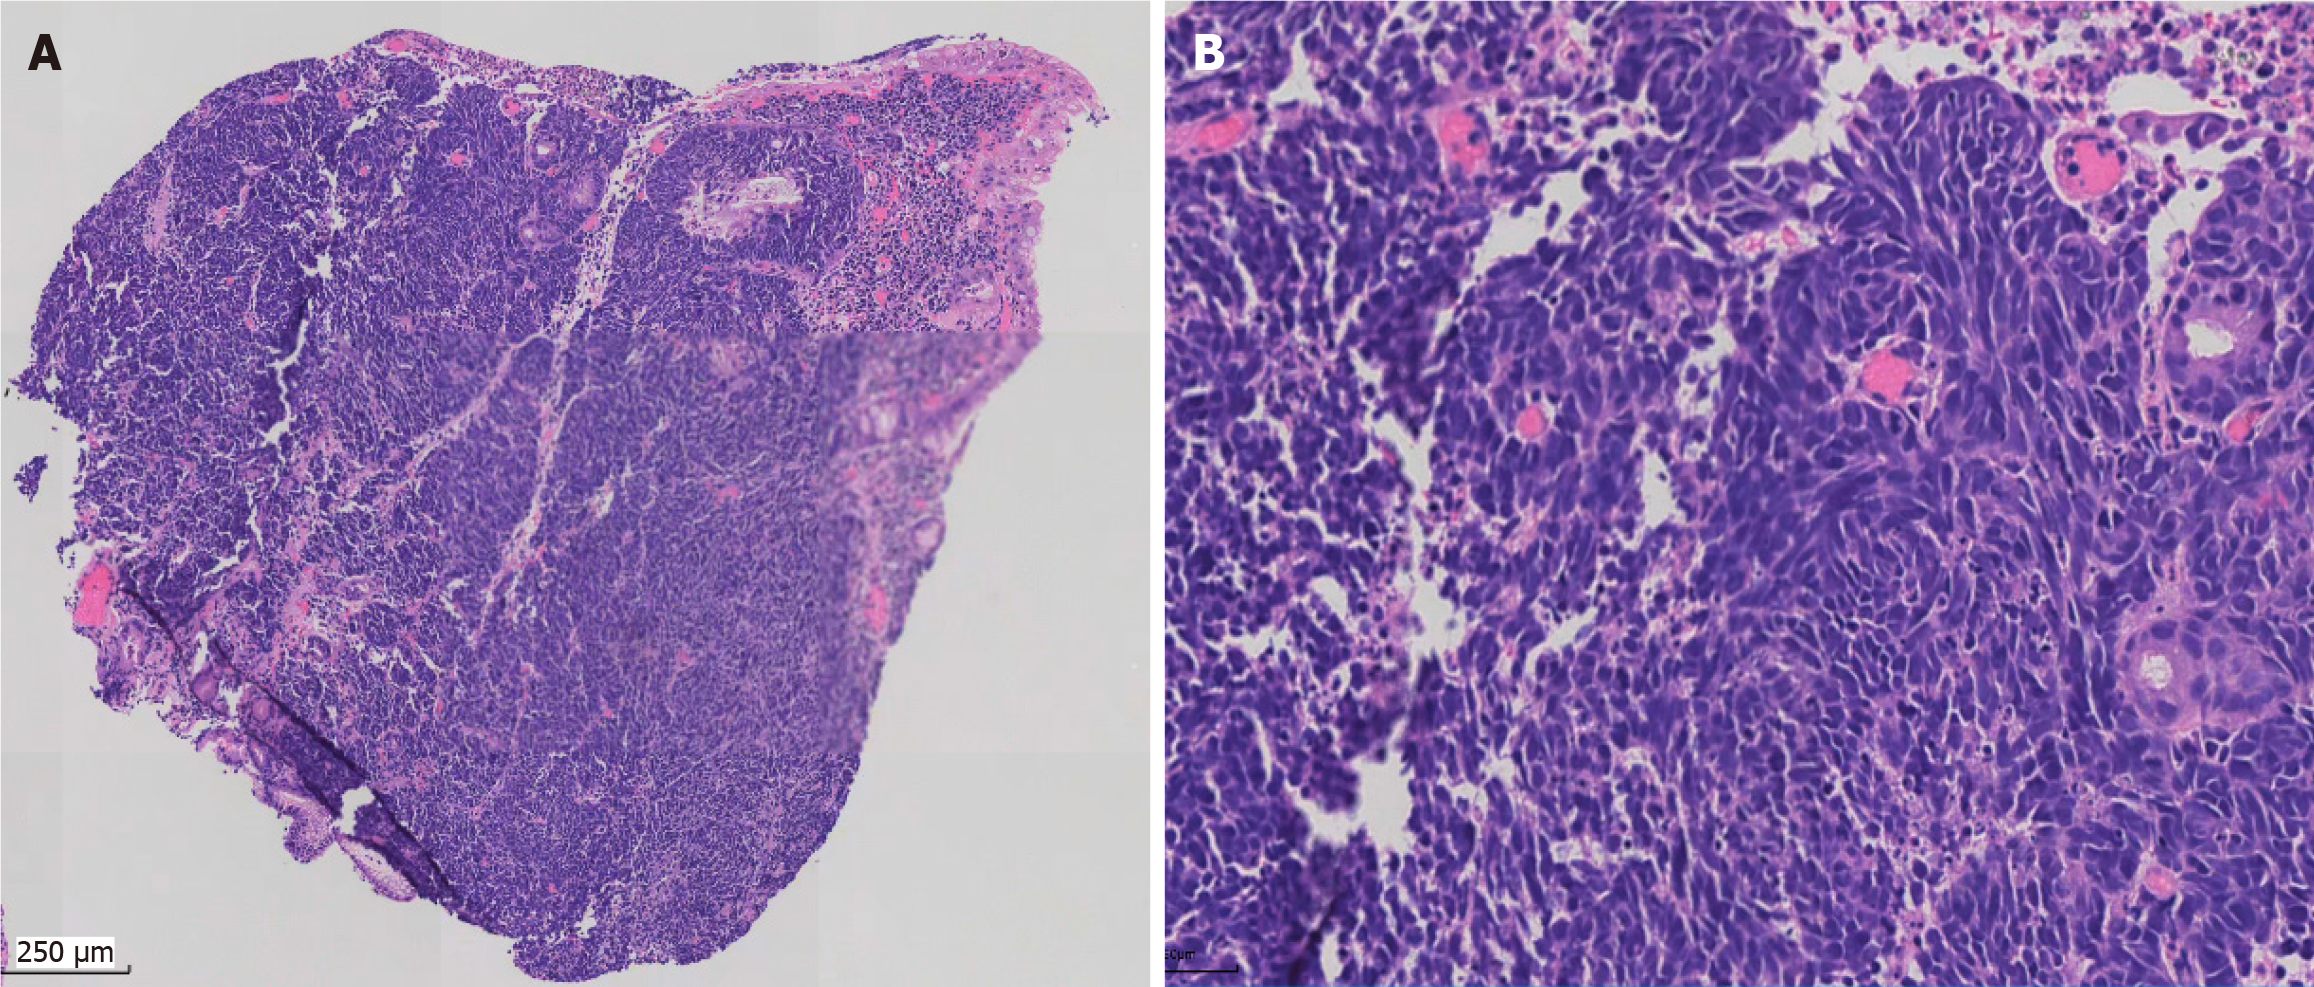

Computed tomography (neck + chest + abdomen; plain scan + enhancement) showed enlarged lymph nodes in the anterior upper mediastinum, occupying space in the greater curvature of the stomach. In addition, multiple intrahepatic metastases with multiple lymph node metastases were observed in the hepatogastric space and around the abdominal aorta (Figure 1). Gastroscopy examination revealed a mass in the gastric body (Figure 2).

During the 16-month follow-up, the tumor in the gastric body and liver showed marked shrinkage, and the size of the lymph nodes also decreased (Figure 1). The patient did not report any specific discomfort, and there was a significant improvement in mental and physical condition.